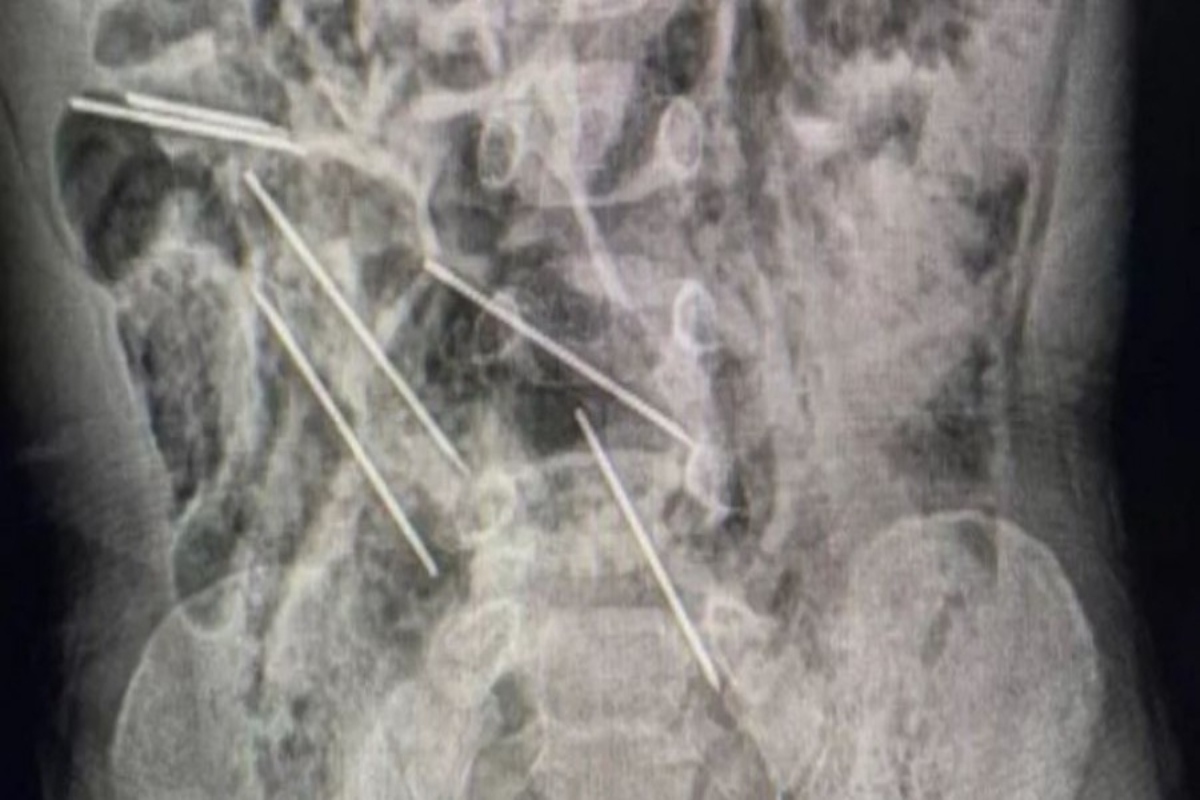

Ο Δρ. Eφρέν Σαλαζάρ είπε ότι έγινε επέμβαση και όταν οι γιατροί άνοιξαν τη κοιλιά του μικρού έκπληκτοι αντίκρισαν τις βελόνες.

«Βρήκαμε αυτά τα μεταλλικά κομμάτια και ξαφνικά συνειδητοποιήσαμε ότι ήταν πραγματικά βελόνες», είπε ο Δρ. Σαλαζάρ.